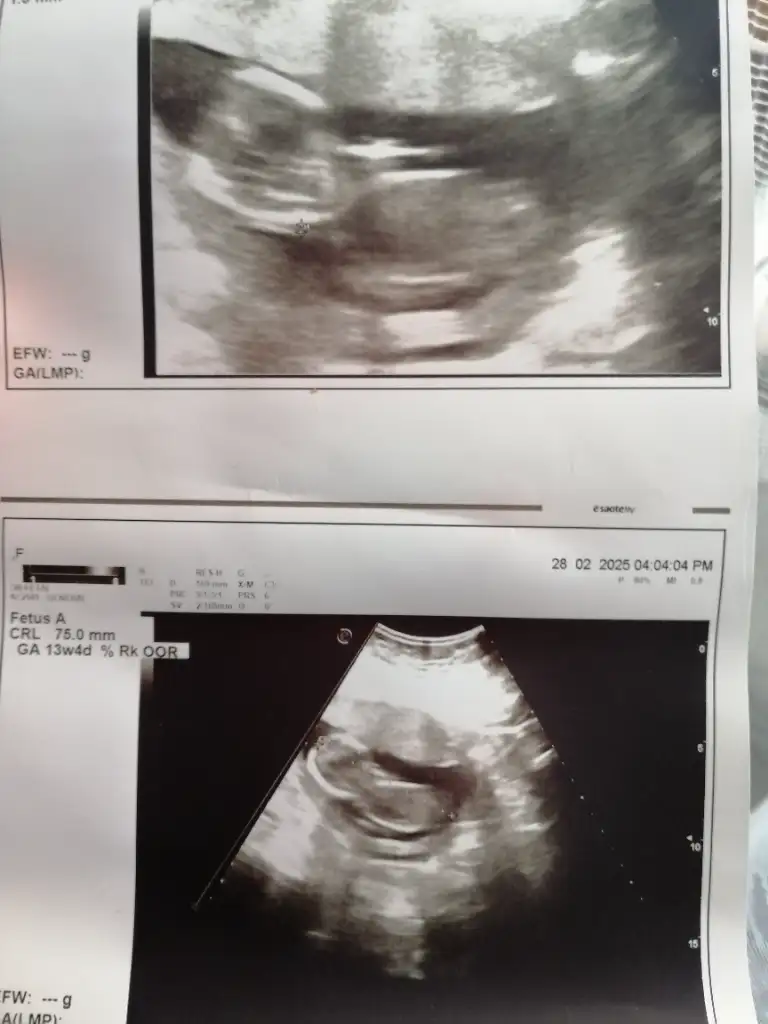

13 haftalik bakarmisiniz nedir sizce

• IMG_5072.webp

IMG_5072.webp

40 KB · Görüntüleme: 156

• IMG_5071.webp

IMG_5071.webp

20,1 KB · Görüntüleme: 102

• IMG_5070.webp

IMG_5070.webp

27,2 KB · Görüntüleme: 108